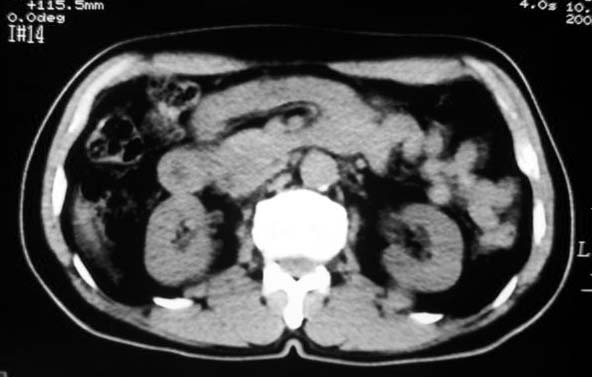

标题: CT7740:男65岁,无明显不适.

定位:病灶位于胃腔外,大弯侧后下方.

特征:实质性肿物,边界清楚,内见低密度影,明显压迫胃壁,并形成切迹.

考虑:脾门淋巴瘤或间质瘤.

考虑胃的肿瘤或胰尾肿瘤,肝右叶后下段低密占位警惕转移。建议增强检查

从这些图像上看,此软组织团块影,在胃腔的外面,胃壁是一种受压的改变,所以考虑此病灶和胃没有关系,建议进一步增强ct检查。

病灶起源于胃壁向腔内外突出,边缘光整,内可见片状低密度区,考虑间质瘤可能性大,建议增强扫描。